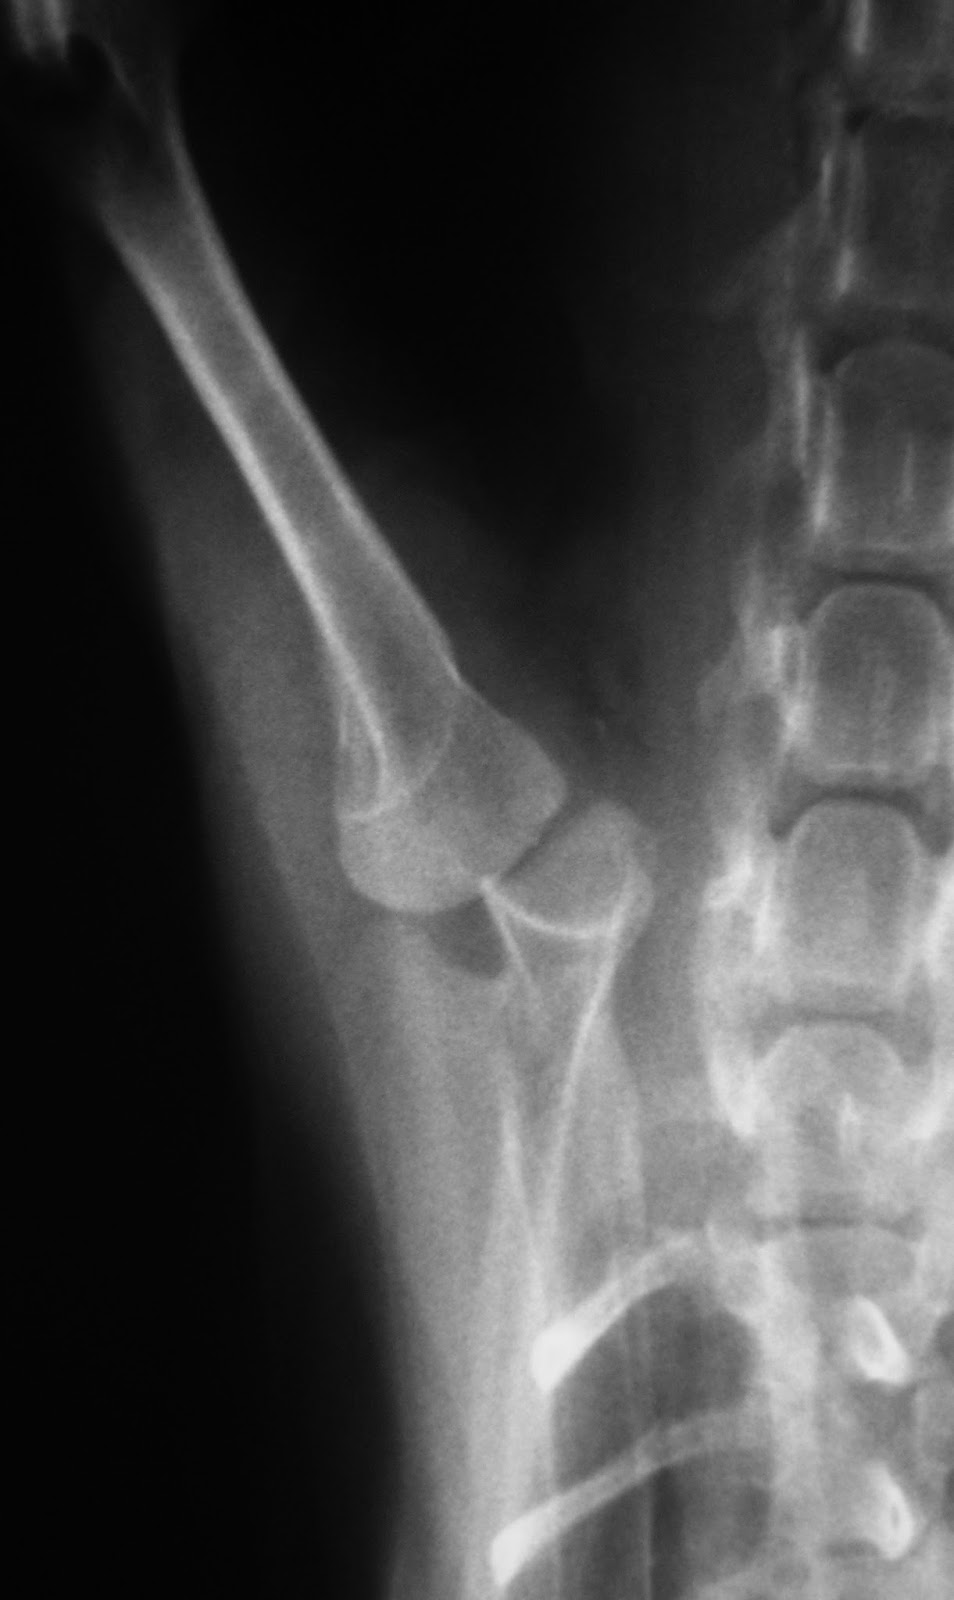

Συντηρητική ανάταξη εξαρθρήματος ώμου από Πέτρος Μπεάκος11/09/201307/12/2017Σχολιάστε Εξάρθρημα ώμου σε νανόσωμο Κανίς (Poodle toy) Μετά την ανάταξη Τοποθέτηση νάρθηκα Κοινοποιήστε: Στείλε ένα σύνδεσμο σε έναν φίλο(Ανοίγει σε νέο παράθυρο) Email Εκτύπωση(Ανοίγει σε νέο παράθυρο) Εκτύπωση Mοιραστείτε στο Facebook(Ανοίγει σε νέο παράθυρο) Facebook Μοιραστείτε στο X(Ανοίγει σε νέο παράθυρο) Χ Μου αρέσει! Φόρτωση... Σχετικά